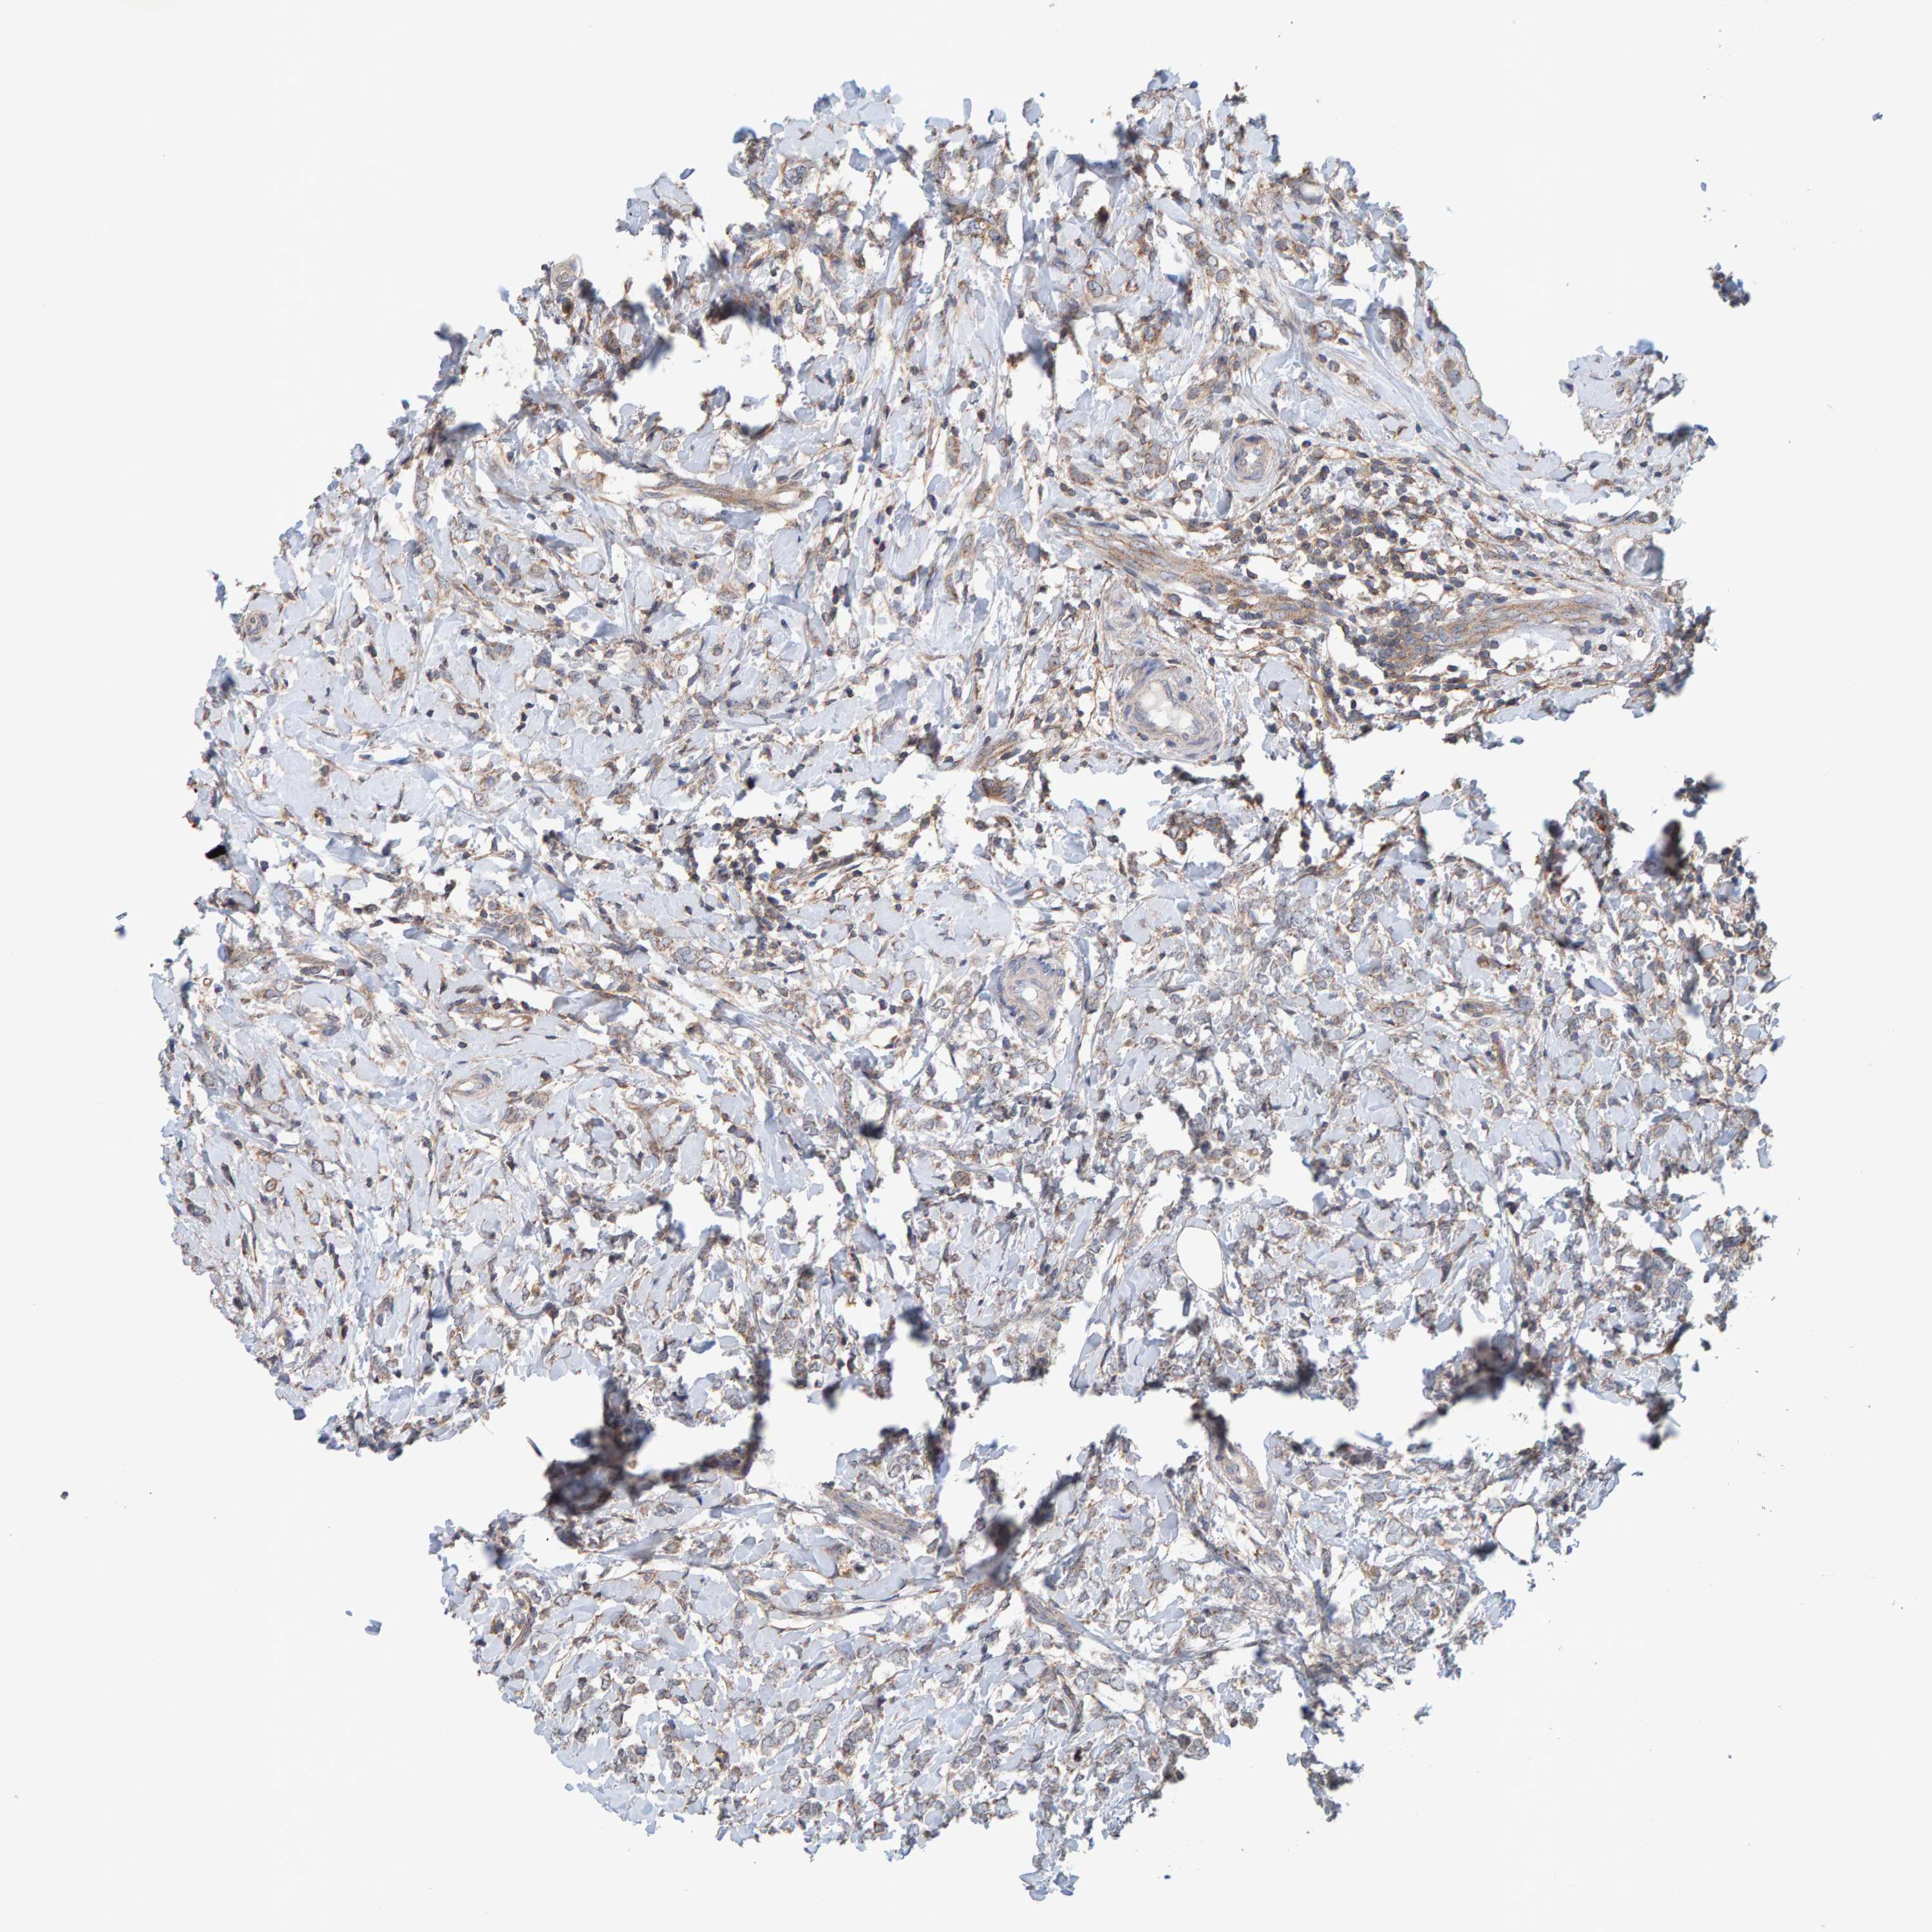

BRCA TCGA BRCA VALIDATION PROTEIN EXPRESSION

ANTIBODIES

AND

VALIDATION